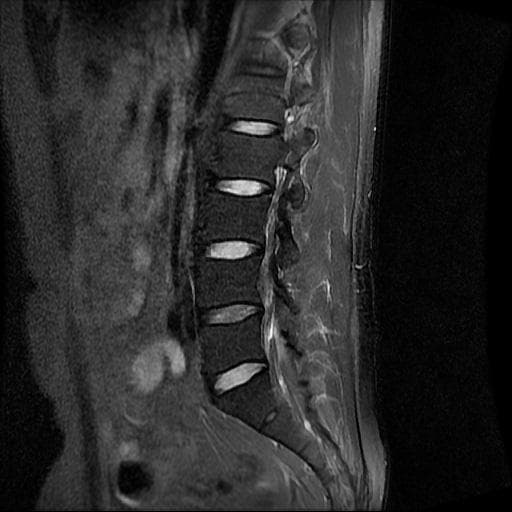

이번에 허리 MRI찍었는데

상태 어떤지 고견 여쭙습니다.

큰 이상이나 문제점은 없어 보이는 것으로 생각되는데요, 허리통증이 지속되는 경우에는 반드시 디스크 질환에 의한것은 아닐 수 있습니다.

현재로썬 디스크 상태는 심하지않는것으로 확인이 됩니다.

MRI 영상 커트로 판독을 할 수는 없습니다.